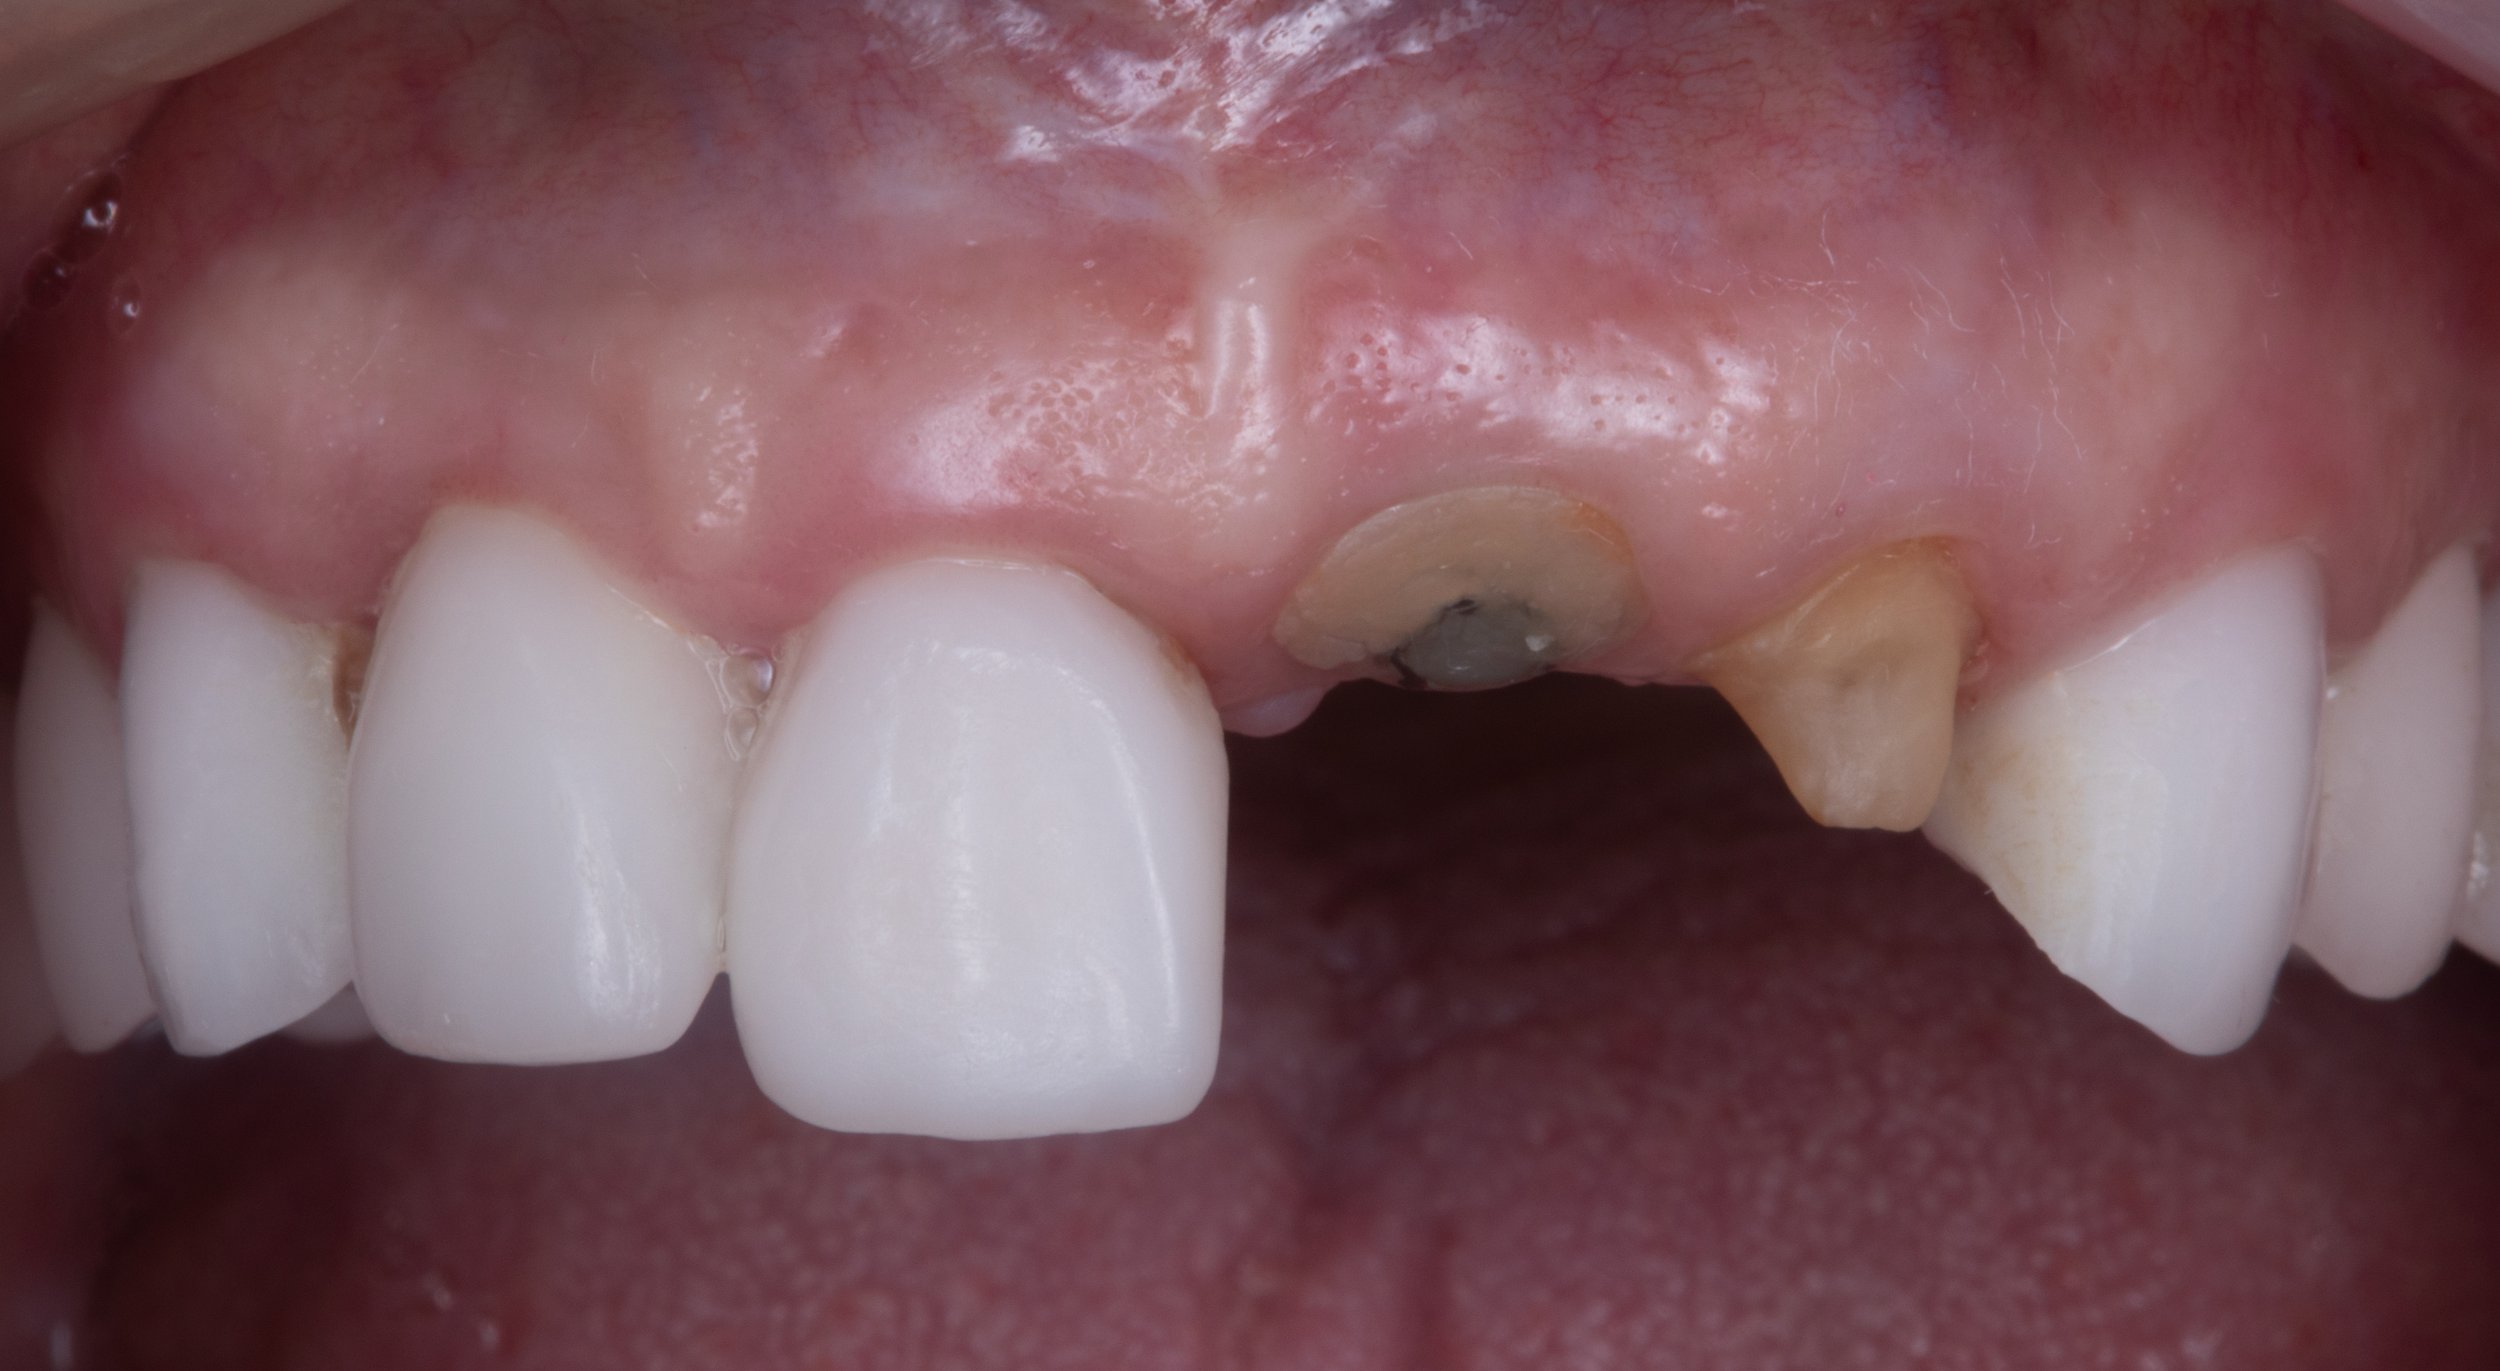

A missing tooth, or one that is badly fractured, or infected may be difficult to restore using conventional dental techniques. Despite our desire to preserve as many natural teeth as possible, the end result of saving a severely compromised tooth may not be functional, predictable, or worthwhile. In these situations, a dental implant may be the best option for tooth replacement. Most cases will take 3-4 appointments over a 6-12 month time span.

Thorough clinical and radiographic planning is important for creating a comprehensive treatment plan. The first step is to gently remove the diseased tooth and any surrounding infection without injuring the adjacent structures. With the proper use of dental anesthetic and careful instrumentation, this process is painless.

A detailed image taken using Cone-Beam Computed Tomography (CBCT), can reveal additional three-dimensional information about the tooth and surrounding structures. If certain conditions exist such as the absence of infection and bone loss, then a dental implant may be placed immediately after the tooth is extracted. This is known as an immediate implant placement.

However, if these conditions are not present, bone grafting may need to be performed first, then followed by delayed implant placement.